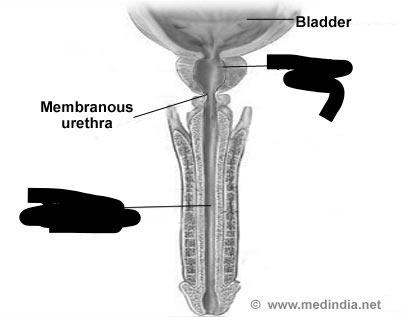

Corpora cavernosa (pl.) Corpus Cavernosum (s.)

Corpus Spongiosum

External urethral orifice (male)

Glans penis

Prepuce (=foreskin)

Prostatic/spongy urethra (males)